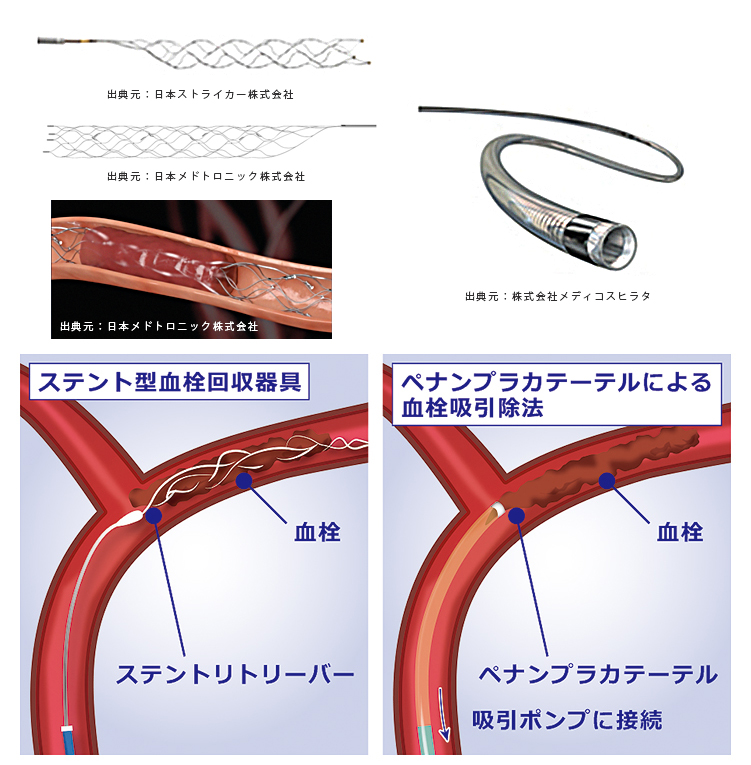

治療で使われるカテーテルにはいくつかのタイプがあります。

一つは“ステント”と呼ばれる金網を用いる方法、もう一つは“吸引カテーテル”と呼ばれる、文字通り血栓を吸引して除去する方法があります。

ステントは心筋梗塞や狭心症の時に細くなった心臓の血管を広げる時に使われているものとして知られております。ただ、血栓回収療法の時は少し違った使い方をします。血栓で詰まったところでステントを広げると、ステントが広がり血栓を押しつぶします。すると一時的に脳の血流が再開します。ただ、このまま様子をみるとステントの金網の中に血栓がめり込みます。そのうちめり込んだ血栓により再度血管が詰まってしまいます。これでは意味が無いのでは、と思ってしまいますが、再度詰まることでステントが血栓に絡んだと判断できます。そうすれば、このステントをゆっくり引くとステントに絡んだ血栓も一緒に引けて来て、ステントを抜去すると血栓も取り除くことができます。うまくいけば、1回で詰まった血栓を除去できます。